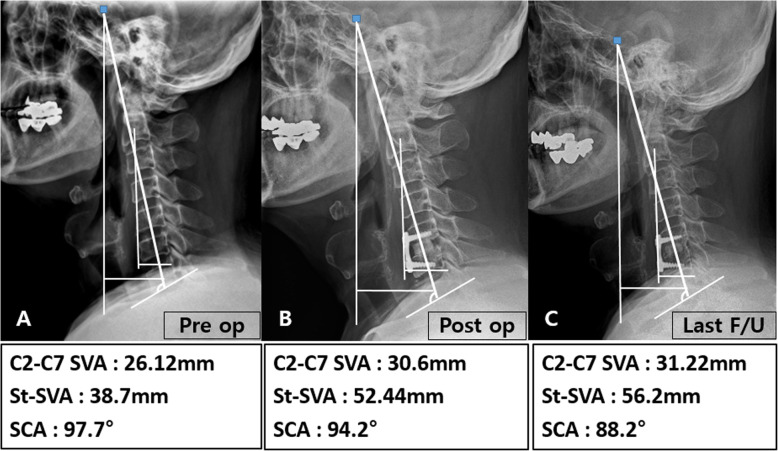

Fig. 4.

A case from the ACDF with complete UPR group. The patient underwent an ACDF operation of C5/6 with complete UPR. In this patient, C2–C7 SVA and St-SVA increased with time, but SCA decreased with time

Fig. 5.

A case from the ACDF without UPR group. The patient underwent an ACDF operation of C4/5 without UPR. In this patient, C2–C7 SVA and St-SVA decreased with time, but SCA increased with time

Cervical lordosis, segmental angle, disc height, C2-C7 SVA, St-SVA, T1 slope, SCA, incidence of subsidence, and fusion rate of the two groups are shown in Table 3. All cervical sagittal parameters, including cervical lordosis, segmental angle, disc height, C2-C7 SVA, St-SVA, T1 slope, and SCA, except for preoperative St-SVA, SCA, and disc height of 2 years follow-up, were similar between the ACDF with complete UPR and ACDF without UPR groups. Differences in disc height, C2-C7 SVA, and SCA at 2-year follow up after preoperative examination, however, were statistically significant (p < 0.05). Subsidence occurred in 9 patients (ACDF with complete UPR: 8 cases [33%] versus ACDF without UPR: 1 cases [4%]; p < 0.05). Radiological images for representative patients in each group are displayed in Figs. 4 and 5. There was no statistical significance because there were only a few cases of removal of uncinate on both sides. However, subsidence occurred more frequently in cases of removal of both sides than in cases of removing only one side.